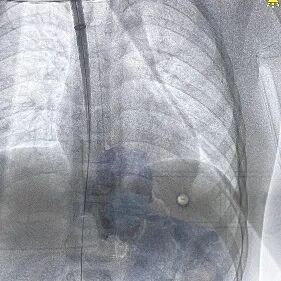

手术在全麻下进行,在超声引导下成功穿刺右侧颈内静脉,置入8F鞘管并提前置入Proglide血管缝合器。经鞘管送入导丝,稳定通路后,将Micra AV递送系统沿导丝轻柔推进,经上腔静脉、右心房进入右心室。术中采用多角度X线透视(LAO 30°、RAO 30°)及心腔内超声(ICE)辅助,精确引导递送系统定位至右室间隔中位。

在确认器械锚定满意,进行电参数测试。结果显示起搏阈值0.5V @ 0.24ms,感知振幅7.7mV,阻抗740 Ω,各项参数均理想。完成测试后释放起搏器,牵拉试验确认固定稳定,手术顺利完成,总操作时间35分钟,无并发症发生。